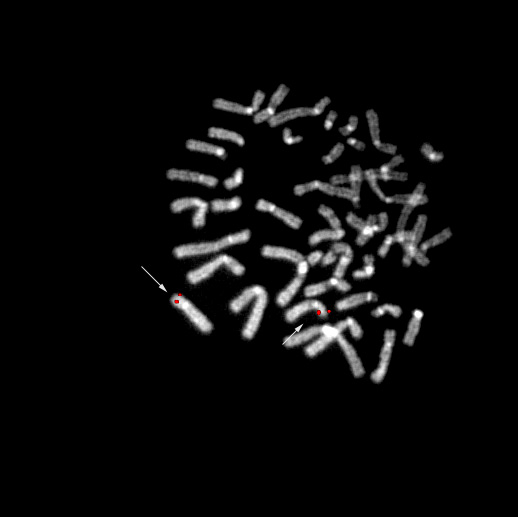

bA1136K1